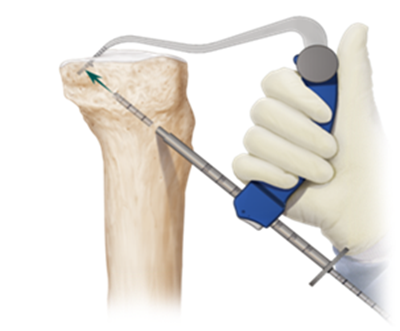

We started the arthroscopic part; we make a neat examination of the joint, proceeding with the repair or removal of meniscal lesions when present. At this point it is frequently observed indemnity Humpry ligament, should not be confused with the PCL. This structure is respected as much as possible. The first thing to be done is a shaving of rasa lag Hoffa, synovial plica and other Posterior Cruciate Ligament remnant. To perform this we also put a postero interanal cannula that allows us to visualize better the tibial insertion of PCL (Foot Print). Once we have a good visualization of the intercondylar, it is very important to visualize the posterior wall of the internal condyle, as this will help us achieve the femoral hole. First we started with the realization of the tibial hole, placing the PM Retrograde Tibial Guide (Constant Guide Arthrex) (Figure 5) wick of 11mm on Foot Print of PCL, (this guide allows us to move back the posterior capsule). We 2mm skin incision on the antero-medial aspect of the tibia and spent the guide pin; the wick is engaged, and always advancing the guide in the direction of clockwise, it begins to pry back, and so it begins to make the tibial hole. Once we have carved a hole, we have to take it back to make the wick have contact with the Retrograde Femoral Guide, and in this moment its placed them in reverse perforator so that the wick can be hooked to the the guide again. Right then the Retrograde Femoral Guide is removed, leaving only the Pin Guide. The rod guide is regulated with markings every 5 mm, allowing us to meet the tibial length. Usually this length is approximately 70mm, being recommended to leave 10mm undrilled so the tibial cortex won’t be violated. Finishing the previous steps, we get through a Fiber stick by the guide pin, which recovered by the PM, thread that will help us to pass the neo-ligament (Figure 6).

Figure 5 Guide flip cutter retrograde